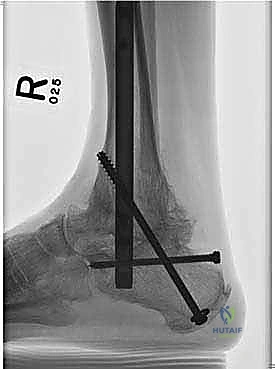

يتم هذا الدمج باستخدام مسمار نخاعي (Intramedullary Nail) طويل وقوي يُدخل من أسفل الكعب ليخترق العظام الثلاثة، ويتم تثبيته ببراغي قفلية لضمان أقصى درجات الثبات. الهدف من إلغاء الحركة في هذه المفاصل التالفة هو القضاء التام على الاحتكاك العظمي الذي يسبب الألم المبرح، مما يوفر للمريض قاعدة ثابتة وقوية للمشي.

4. إدخال المسمار النخاعي

يتم عمل شق صغير أسفل الكعب. يتم إدخال سلك توجيهي، يتبعه إدخال المسمار النخاعي القوي المصنوع من التيتانيوم. يخترق المسمار عظمة الكعب، ثم يمر عبر عظمة الكاحل، ليستقر أخيراً داخل القناة النخاعية لعظمة الساق.

5. التثبيت بالبراغي القفلية (Locking Screws)

لضمان عدم تحرك المسمار أو دوران العظام حوله، يتم تثبيت المسمار ببراغي عرضية تخترق العظام والمسمار معاً من الأعلى (في الساق) ومن الأسفل (في الكعب والكاحل). يتم استخدام جهاز التصوير الإشعاعي (C-arm) داخل غرفة العمليات للتأكد من الموضع المثالي لكل مسمار.